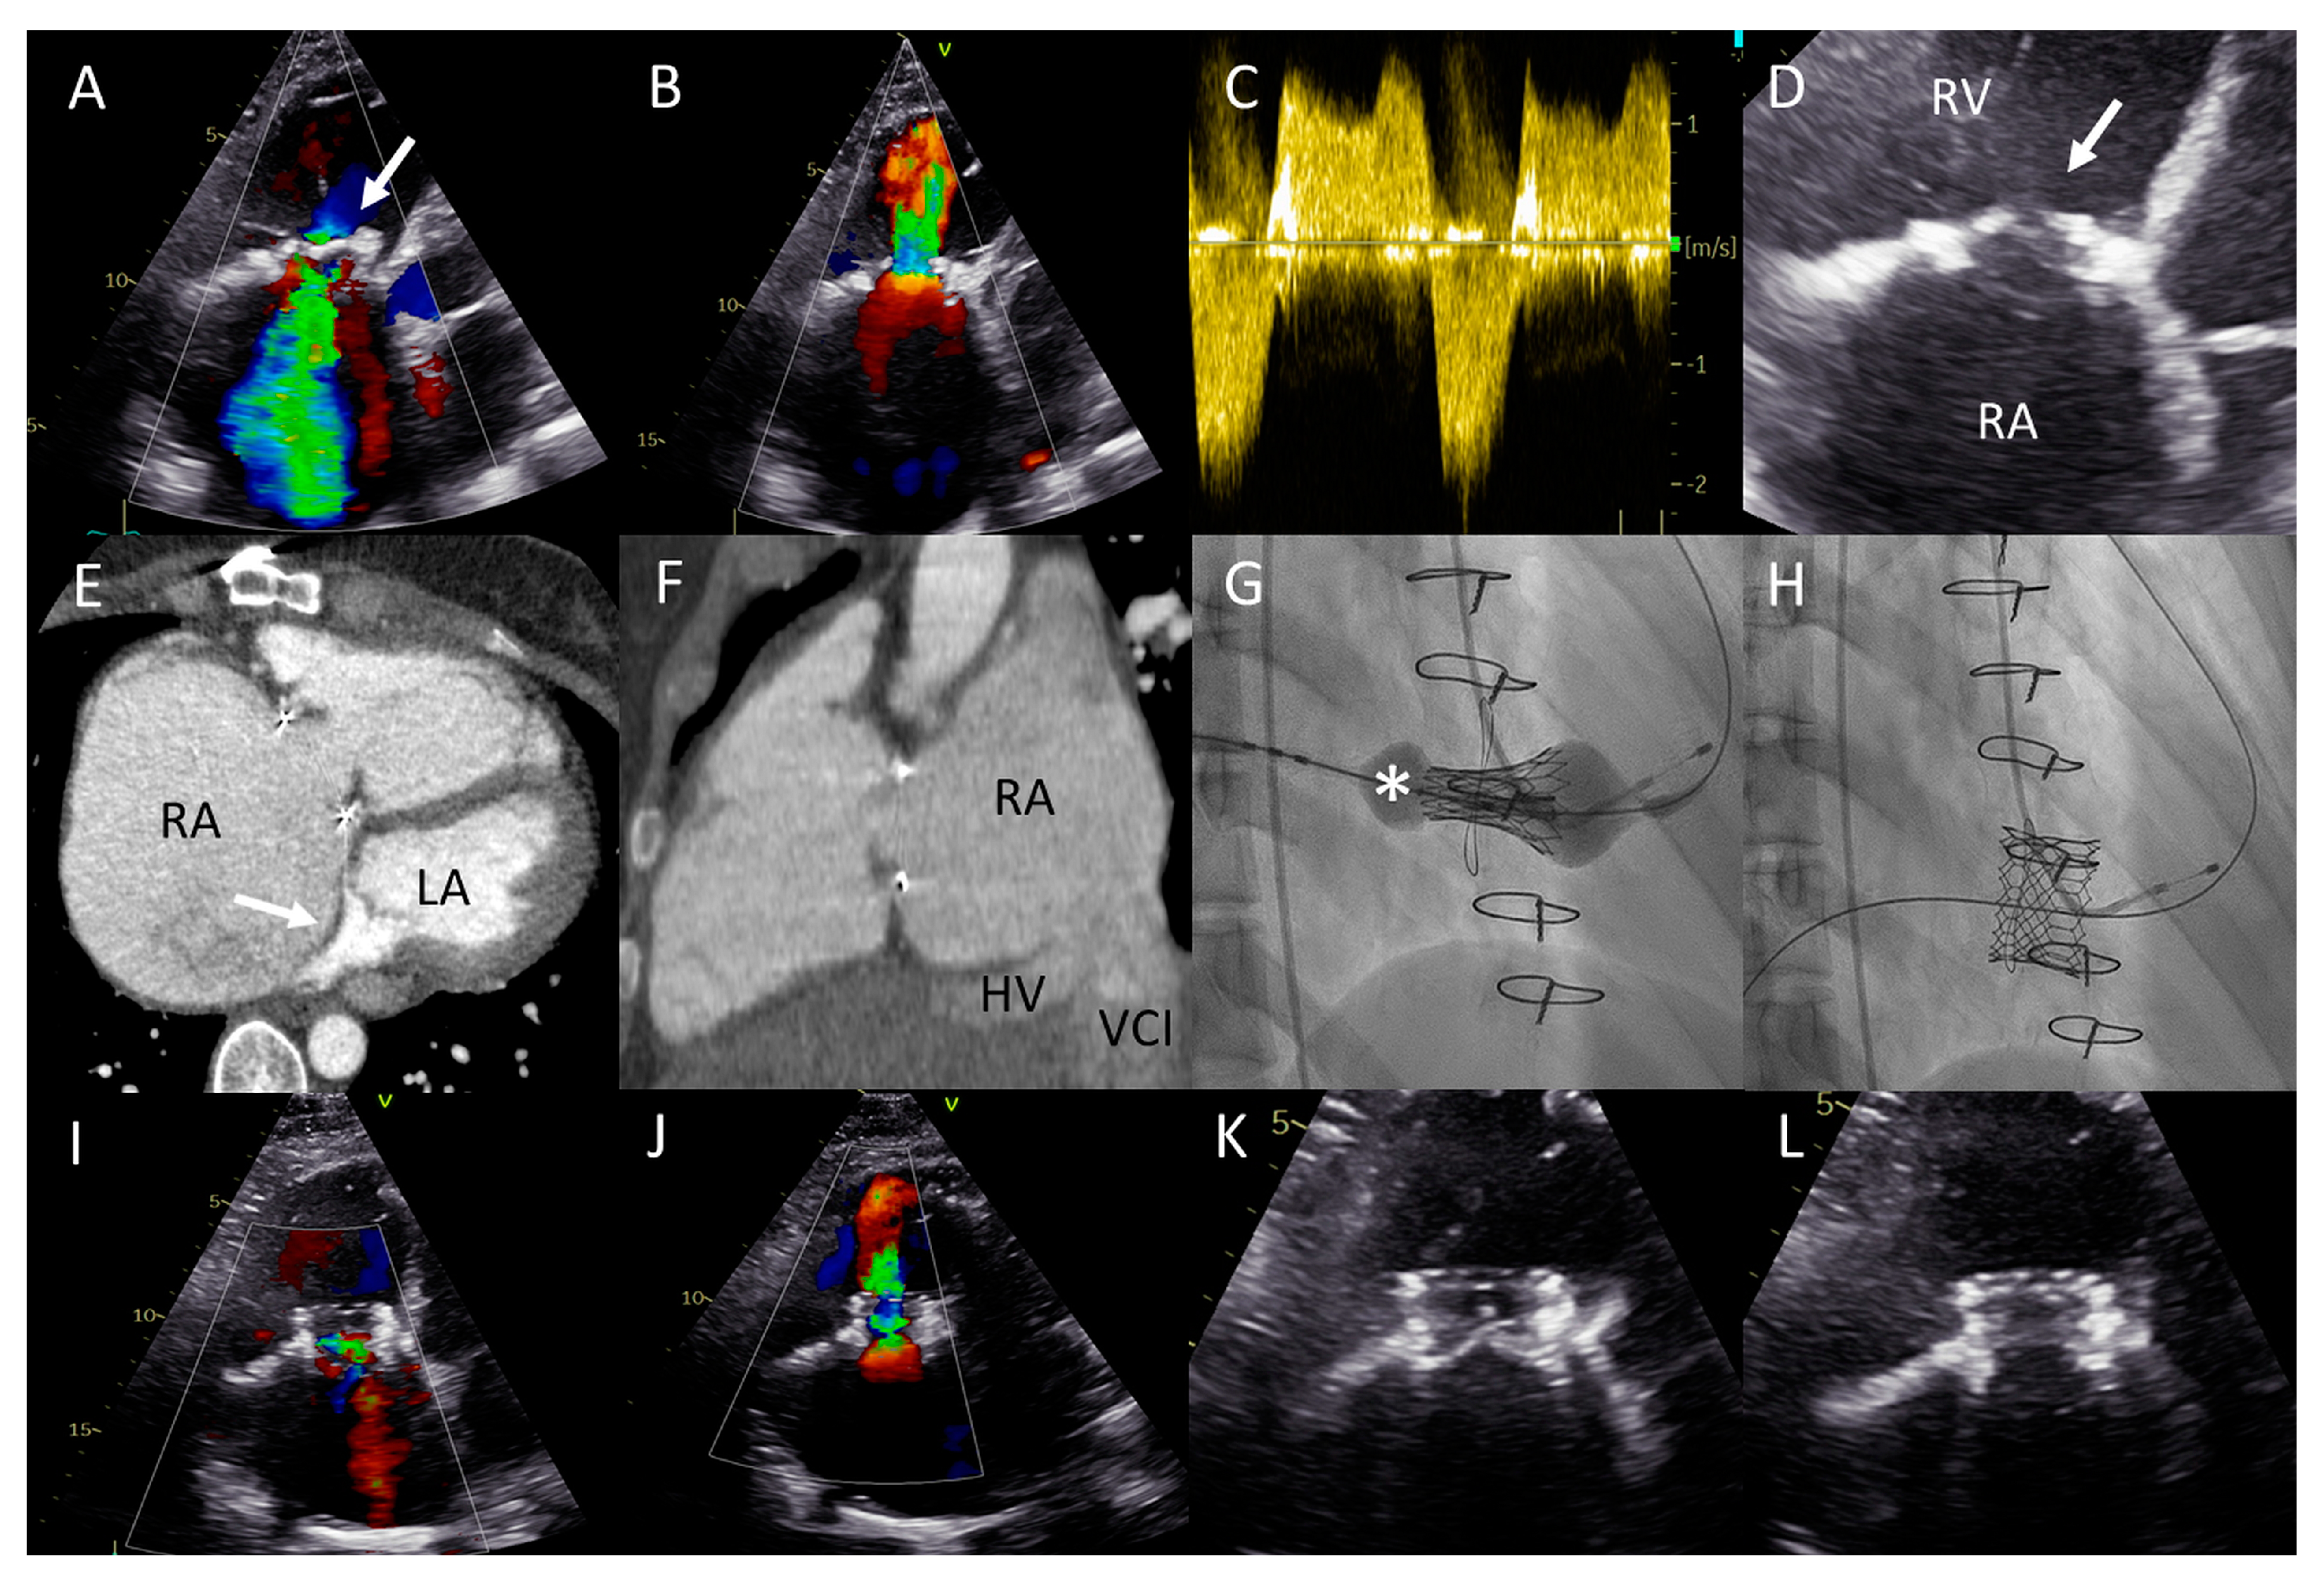

(A) Color Doppler apical four-chamber view shows severe tricuspid regurgitation (TR) with a wide vena contracta (arrow) and a systolic jet reaching the roof of the enlarged right atrium (RA). (B) Color Doppler showing turbulent inflow through the tricuspid valve (TV) bioprosthesis and aliasing, mean gradient was elevated at 4–5 mmHg. (C) Continuous wave Doppler showing a dense TR signal with low velocity. (D) Calcified and degenerated tricuspid bioprosthesis (arrow). (E) Axial slice through a computed tomography (CT) scan at the level of the right ventricle shows a giant RA and an intra-atrial septum deviation towards the left atrium (arrow), partially suppressing it. (F) Sagittal CT slice shows the inflow angle of the inferior vena cava-right RA and the RA-TV. Note the distended hepatic vein (HV). (G,H) Right anterior oblique fluoroscopy projections show the expansion of the Sapien 3 valve (asterisk) using the ring of the degenerated bioprosthesis as the reference and the final result, respectively. (I,J) Apical four-chamber color Doppler views showing normal function of the valve-in-valve bioprosthesis (appreciate the difference with (A,B), respectively). (K,L) View of the valve-in-valve bioprosthesis in systole (closed) and diastole (open), respectively.

This was successfully performed under local anesthesia, by means of right femoral access and fluoroscopy and TTE guidance. A temporary pacemaker wire was placed in the left ventricle and the AgilisTM steerable introducer (Abbott, IL, USA) was used to safely access the RA, given the relatively sharp angle between the vena cava-RA and the RA-RV axis (Figure 4F). The Edwards eSheath TM (Edwards Lifesciences, USA) was then used to implant a 29 mm Edwards SAPIEN 3 valve (Edwards Lifesciences) in the TVR bioprosthesis under rapid pacing (Figure 4G,H). Normal function of the new valve-in-valve bioprosthesis was confirmed by transthoracic echocardiography (Figure 4I–L). The periprocedural course was uneventful. At 22 months follow-up, the patient is in NYHA functional class I with moderately reduced (yet significantly improved) RV function and normal function of the bioprosthesis.